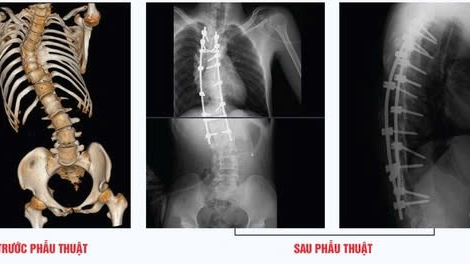

Bộ Y tế cho biết, dự thảo Luật sửa đổi, bổ sung một số điều của Luật Bảo hiểm y tế (Luật BHYT 2024) đang được lấy ý kiến của các bộ, ngành, địa phương và theo dự kiến sẽ được trình Quốc hội xem xét, cho ý kiến tại kỳ họp tháng 10 này. - Các bác sĩ tại Bệnh viện Đa khoa Thành phố Vinh đã phẫu thuật thành công cho một thanh niên 23 tuổi mắc chứng vẹo cột sống nghiêm trọng, với cột sống bị cong như hình chữ "S".